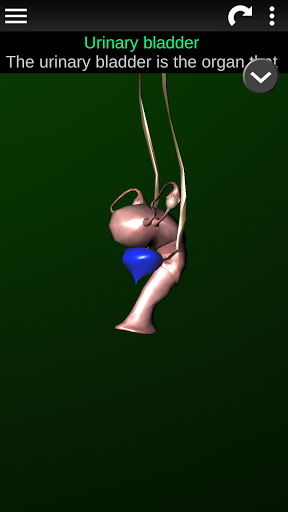

Menampilkan model anatomi 3D dari organ utama tubuh manusia dan penjelasannya masing-masing.

* Deskripsi masing-masing organ.